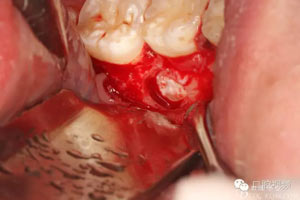

圖8.繼續(xù)去骨、暴露整個35牙冠。注意牽拉力度。

圖9.分牙、分別取出牙冠和牙根